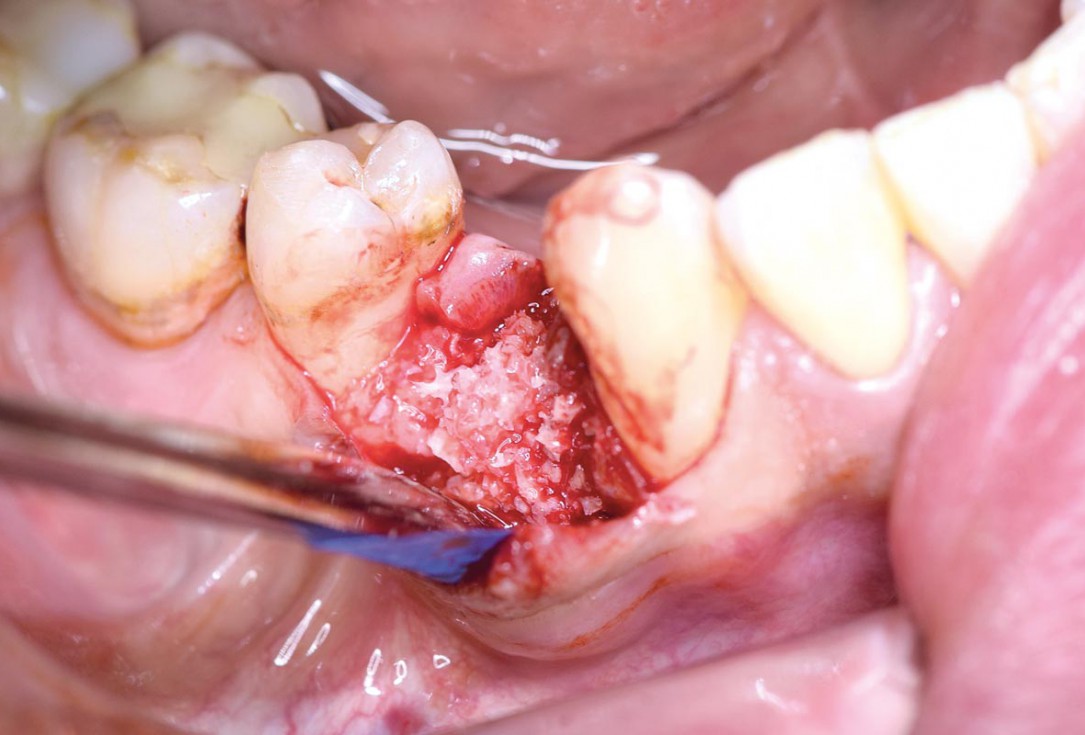

Posterior socket preservation using maxgraft® and permamem® - Dr. C. Landsberg